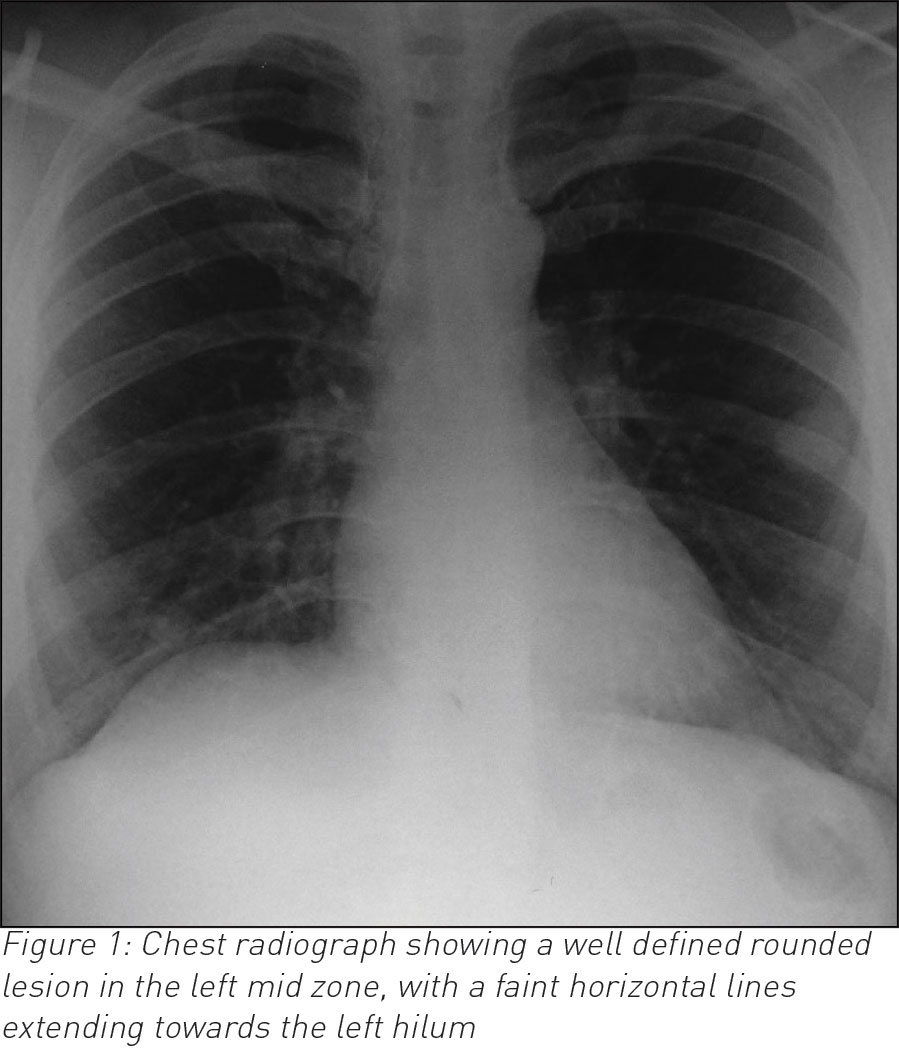

A 35-year-old male, who is otherwise fit and healthy, presented with a 10-day history of cough and temperature. Bloods showed raised white cell count otherwise normal. Chest infection was suspected and a chest radiograph was requested. The latter showed a well-rounded soft tissue opacity in the left midzone with possibly a connecting vessel radiating to the hilum. Two smaller opacities were identified in the right lung. A computed tomography (CT) pulmonary angiogram with intravenous contrast followed and that confirmed the diagnosis of a PAVM of 2cm in the left upper lobe and exquisitely demonstrated the feeding artery and vein with further smaller PVMs of 1cm in the right lung. The patient declined any further intervention.